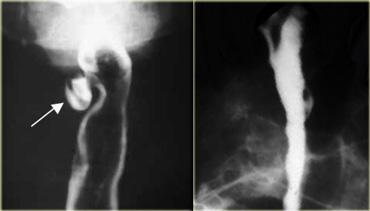

TRÁI: Thực quản giãn (mũi tên) biểu hiện là cấu trúc dài, bờ rõ nét song song với tim. PHẢI: Thực quản giãn thường lệch sang phải. Hẹp (mũi tên) tại khe hoành.

Achalasia

Hình ảnh chụp thực quản:

- Giãn thực quản kèm mất nhu động

- Hẹp thuôn nhẵn tại khe thực quản của cơ hoành

- Ung thư đoạn xa có thể giả dạng achalasia (giả achalasia)

TRÁI: CT cho thấy thực quản giãn (mũi tên) dẫn đến chỉ định chụp thực quản. PHẢI: Chụp thực quản cho thấy hẹp (mũi tên) tại mức khe hoành.